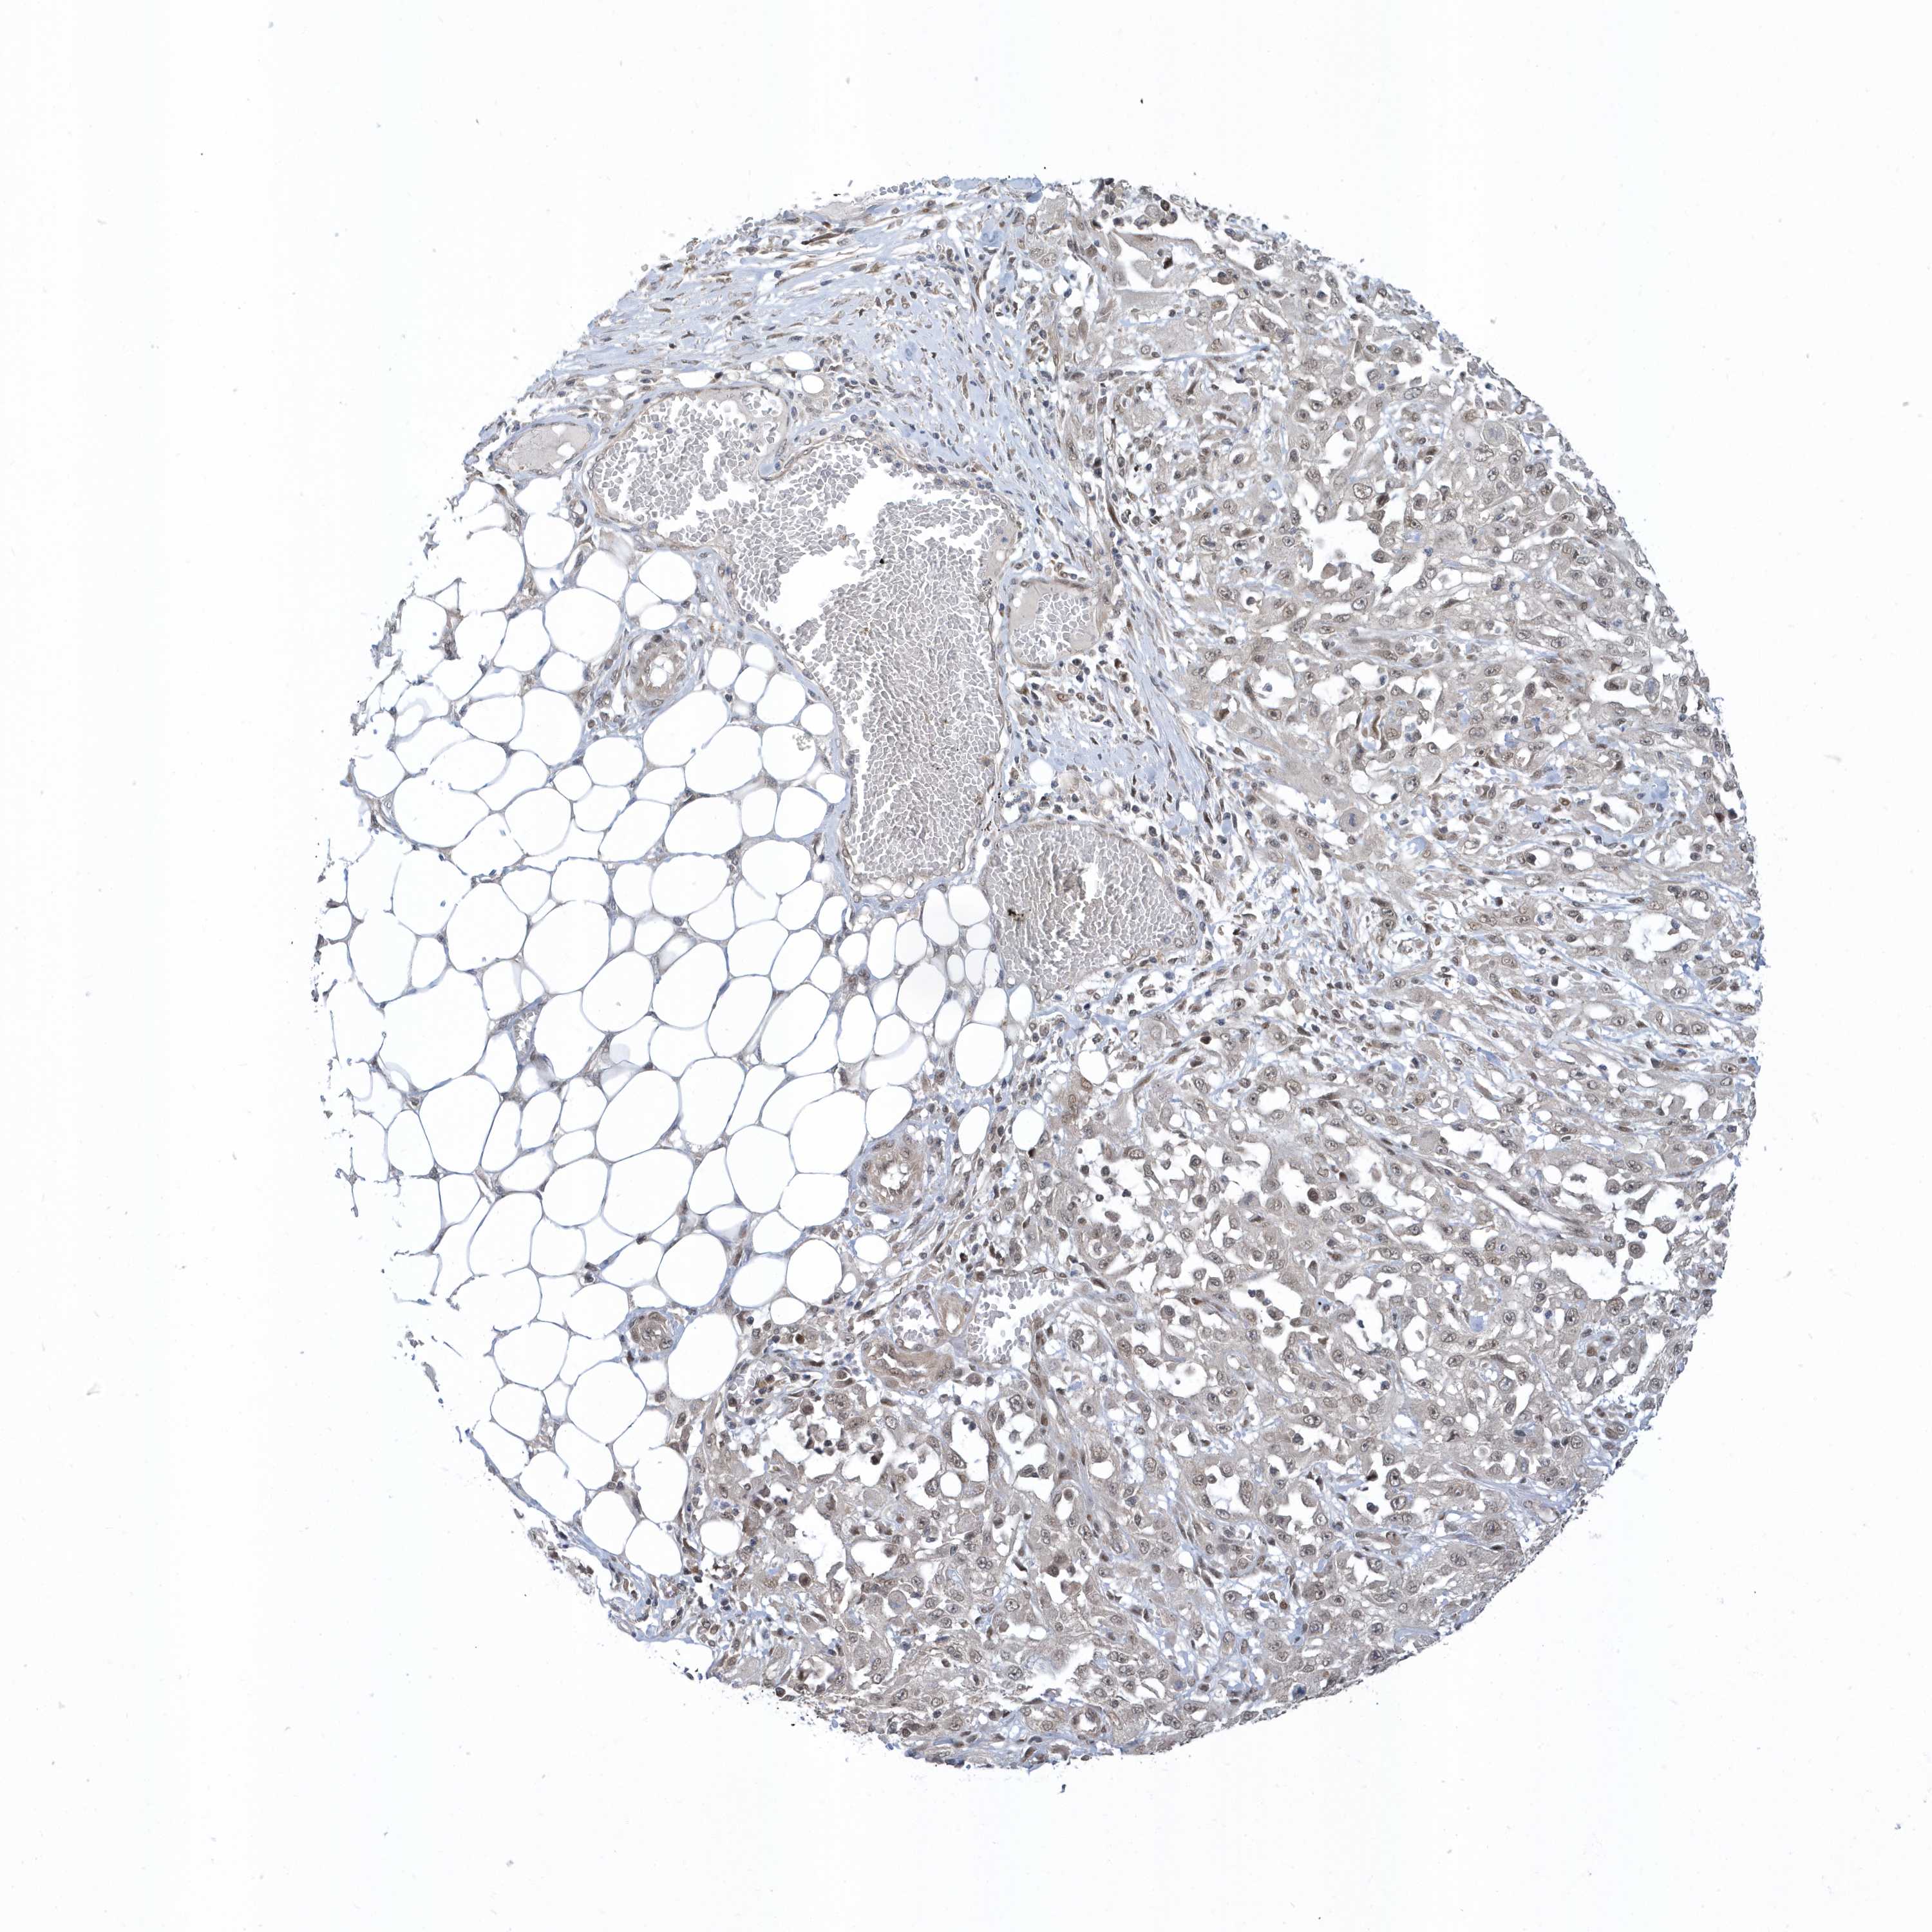

SKIN CANCER - Protein expressioni

A mouse-over function shows sample information and annotation data. Click on an image to view it in a full screen mode. Samples can be filtered based on level of antibody staining by selecting one or several of the following categories: high, medium, low and not detected. The assay and annotation is described here.

Antibody staining in the annotated cell types in the current human tissue is reported as not detected, low, medium, or high, based on conventional immunohistochemistry profiling in selected tissues. This score is based on the combination of the staining intensity and fraction of stained cells.

Each image is clickable and will lead to virtual microscopy that enables deeper exploration of all samples and also displays staining intensity scores, fraction scores and subcellular localization as well as patient and tissue information for each sample.

Antibody HPA035844

Antibody HPA035845

Staining

High

Medium

Low

Not detected

Intensity

Strong

Moderate

Weak

Negative

Quantity

>75%

75%-25%

<25%

None

Location

Nuclear

Cytoplasmic/membranous

Cytoplasmic/membranous,nuclear

Basal cell carcinoma

Squamous cell carcinoma, NOS

Squamous cell carcinoma, metastatic, NOS